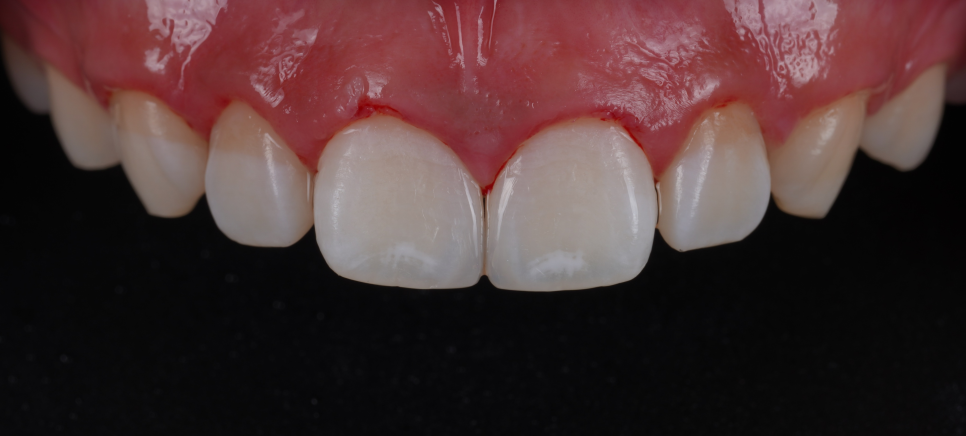

자연스럽게 메꿔진 앞니 사이 공간

촬영 : 251030

치료를 마친 뒤 거울로 확인하더니 “이제 자신 있게 웃을 수 있겠어요!”라고 하시더라고요^^

이번 케이스는 단순히 틈이 있었던 게 아니라 치아 형태 자체가 항아리처럼 끝이 좁아져 실제보다 더 벌어져 보이던 상황이었는데요.

단순히 공간을 채우는 게 아니라 치아의 모서리 라인과 각도를 조정해 형태 자체를 교정하는 데 중점을 뒀습니다.

앞니 레진 치료는 ‘공간을 채운다’보다 ‘형태를 다시 만든다’는 개념에 가까워요.

이번 케이스처럼 치아 형태 때문에 벌어져 보이는 경우는 색감보다 곡선, 각도, 비율이 훨씬 중요해요.